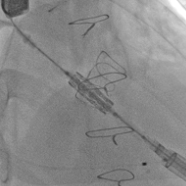

瓣膜释放